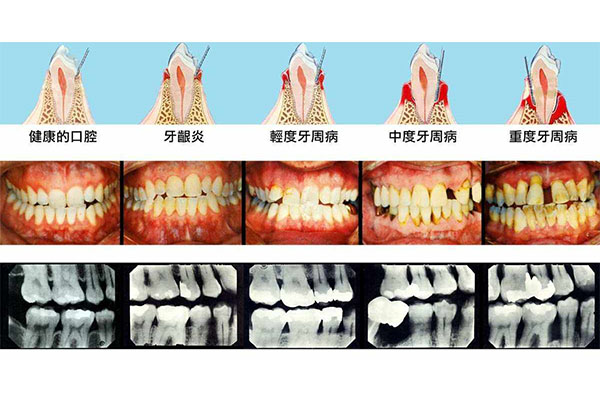

牙周炎是中老年人常见的口腔问题之一,它不仅影响牙齿健康,还可能导致牙齿松动甚至脱落。很多人对牙周炎的起因感到困惑,不知道为什么自己会患上这种疾病。其实,牙周炎的形成是一个长期积累的过程,与多种因素密切相关。今天,我们就来详细解析牙周炎的起因,并结合【中老年口腔】的专业解决方案,帮助您更好地预防和治疗牙周炎,守护您的口腔健康。

牙周炎的早期症状包括牙龈红肿、出血、口臭以及牙齿敏感等。如果您发现刷牙时牙龈出血,或者牙齿周围有轻微的松动,这些都是牙周炎的警示信号。及时就医并采取有效的治疗措施,可以避免病情进一步恶化。